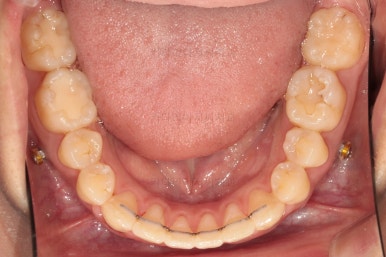

치열의 고른 느낌 좋고요.

덧니, 교합, 중앙선 등 모든게 좋아졌네요.

부산치아교정치과 전후 비교해 보겠습니다.

교합, 맞물림, 중앙선, 덧니, 입매, 앞니위치 및 각도 모든게 잘 마무리 되었습니다.

비발치로 오히려 입이 들어가게(악궁확장이나 치간삭제(공간확보의 목적) 없이도) 할 수 있었던 부산치아교정치과 좋은 치료였습니다.